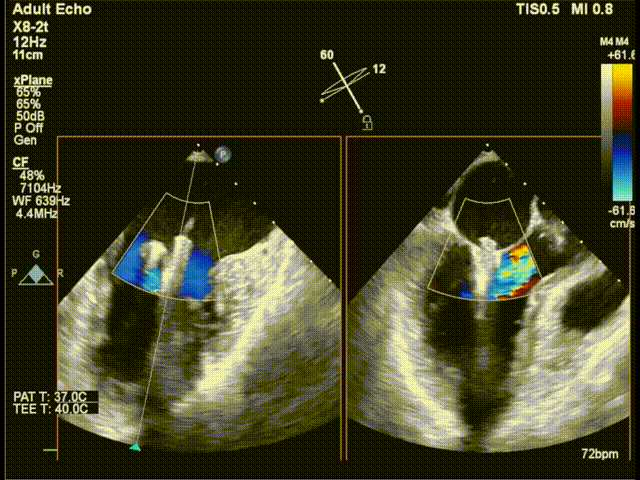

三尖瓣

三尖瓣反流以膈叶脱垂为主,反流主要集中在前叶和膈叶间,从中心区向边缘区的蔓延。后叶又有分了两个叶,分型上属于IIIb型的三尖瓣反流。

三尖瓣膈叶前叶

三尖瓣膈叶前叶color